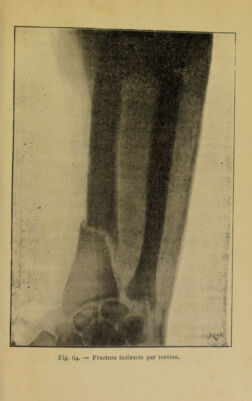

Hygiène du chauffeur : le moteur humain / par R. Bommier ; préface du Comte Mortimer-Mégret.